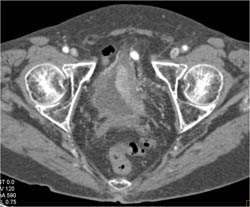

Bladder Cancer